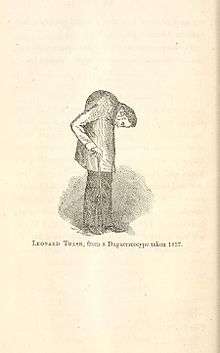

உடற்கூறு நிபுணரும், அறுவை சிகிச்சை நிபுணருமான ரீல்டோ கொலம்போ என்பவர், இந்த நோய் என்னவென்பதை 1559ஆம் ஆண்டில் விவரித்துள்ளார்,[22] மற்றும் 1691 -ஆம் ஆண்டில் தம்ப முள்ளந்தண்டழலால் பாதிக்கப்பட்டிருக்கக்கூடிய ஒரு முதுகெலும்பு கூட்டில் மாற்றங்கள் இருப்பது பெர்னார்டு கான்னர் என்பவரால் வெளியிடப்பட்டது[23]. 1818 -ஆம் ஆண்டில், பெஞ்சமின் பிராய்டி என்பவர் தம்ப முள்ளந்தண்டழல் மற்றும் அதனுடன் இரிடிஸ் ஆகிய நோய்கள் இருப்பதை முதன்முதலில் ஆவணப்படுத்தினார்[24]. 1858 -ஆம் ஆண்டில், டேவிட் டக்கர் என்பவர், லியோனார்டு ட்ராஸ்க் என்ற பெயருள்ள நோயாளி ஒருவருக்கு, தம்ப முள்ளந்தண்டழலின் காரணத்தினால் முதுகெலும்பு பிறழ்வடைந்துள்ளதை விவரிக்கும் ஒரு கையேட்டை வெளியிட்டார்.[25] 1833 -ஆம் ஆண்டில், ட்ராஸ்க் ஒரு குதிரையிலிருந்து கீழே விழுந்தார், இதனால் நிலைமை இன்னும் மோசமாகி பிறழ்வு தீவிர நிலையை அடைந்தது என்று டக்கர் குறிப்பிடுகிறார். இதுவே அமெரிக்காவில் தம்ப முள்ளந்தண்டழல் நோய் முதன்முதலில் பதிவு செய்யப்பட்ட நிகழ்வாகும், ஏனெனில் இதிலேதான் சந்தேகத்துக்கு இடமின்றி, தம்ப முள்ளந்தண்டழல் நோயின் குணநலனான, வீக்கம் தொடர்பான நோயையும், தம்ப முள்ளந்தண்டழலால் ஏற்படக்கூடிய பிறழ்வும் விவரிக்கப்பட்டுள்ளன.